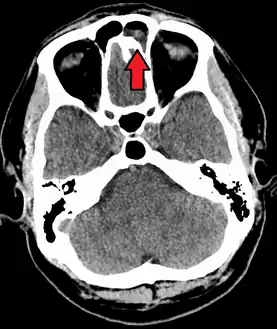

CT of chronic sinusitis

CT scan of chronic sinusitis, showing a filled right maxillary sinus with sclerotic thickened bone